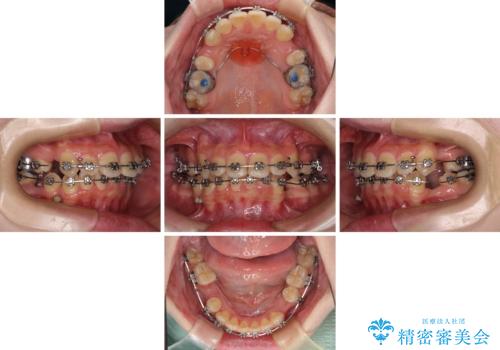

- 矯正装置

- メタルブラケット

非抜歯矯正で歯列を整えると、治療後に口元が今よりも突出する可能性が高かったため、上下左右の小臼歯4本を抜歯し、ワイヤー装置にて矯正治療を行うこととしました。

右上の八重歯の影響で、右側は上顎歯列が前方位の咬み合わせとなってしまっていたため、上顎は第一小臼歯を、下顎は第二小臼歯を抜歯することで咬み合わせや上下正中を調整することとしました。

第二小臼歯抜歯の治療となったため、やや時間はかかりましたが、概ね予想通りの期間で治療を終えることができました。